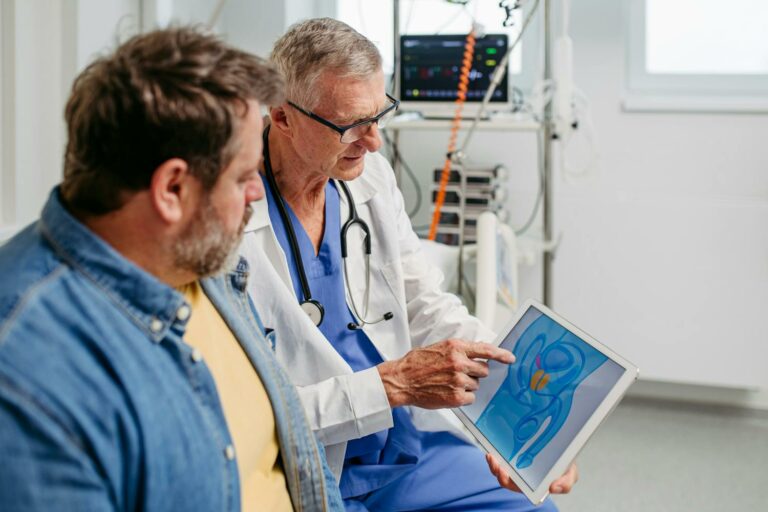

Soulager les hémorroïdes naturellement : les glaçons sont-ils efficaces ?

Aussi étrange que cela puisse paraître, appliquer des glaçons sur des hémorroïdes douloureuses peut soulager l’inconfort. Encore faut-il savoir comment le faire sans aggraver la situation… Découvrez les conseils de Catherine Gaucher, dermatologue. Aussi étrange que cela puisse paraître, appliquer…